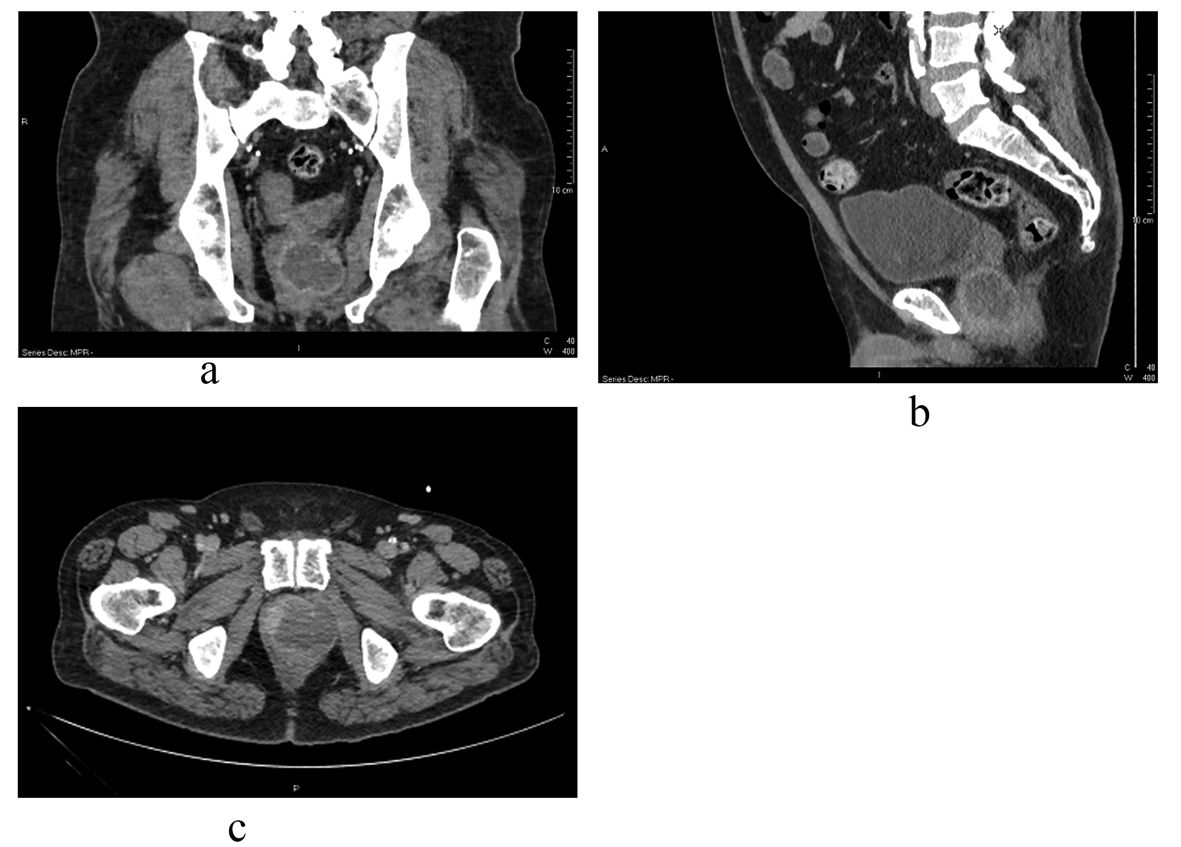

Xanthogranulomatous Prostatitis Presenting as a Prostatic Abscess: Case Report and Review of Literature

Figures